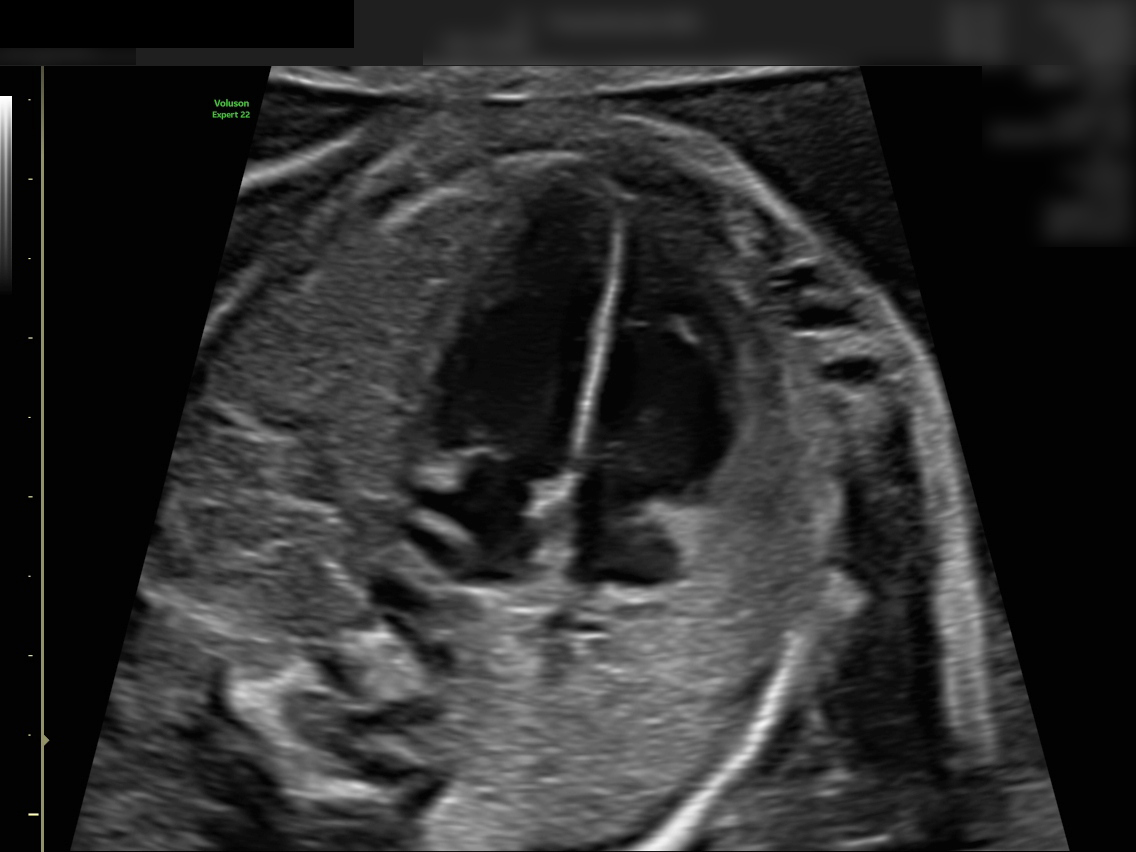

Die Feindiagnostik kann bei uns zwischen der 20. und 21. Schwangerschaftswoche durchgeführt werden.

Diese Untersuchung ist deutlich ausführlicher als der reguläre Ultraschall nach Mutterschaftsrichtlinien. Sie erfordert spezielle Geräte und langjährige Erfahrung des untersuchenden Arztes.

Die Dauer beträgt in der Regel 30 bis 40 Minuten, abhängig von der Lage des Kindes und der Beschaffenheit der Bauchdecke.